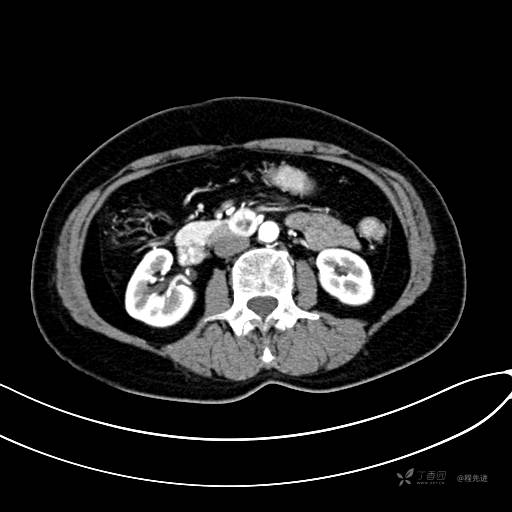

CT增强静脉期